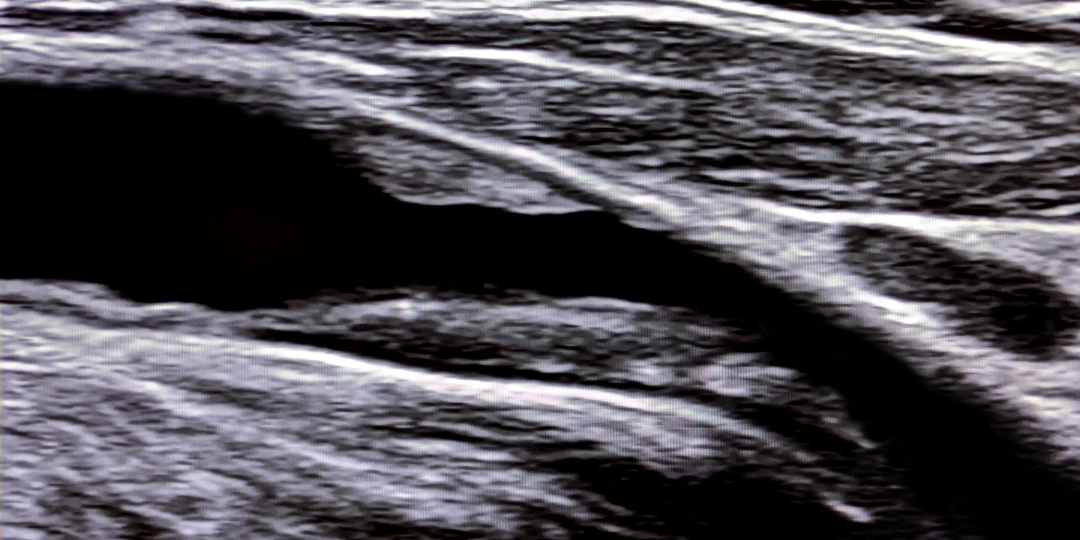

Нашли бляшку со стенозом 30%. Это опасно?

Бывает, пациент приходит с результатом уже выполненного ультразвукового исследования сосудов и задаёт один и тот же вопрос. В заключении описана атеросклеротическая бляшка и стеноз - когда 25%, когда 30%, а когда и больше. Значит ли это, что сосуд уже перекрыт значительно и впереди инфаркт или инсульт? Стеноз 30% означает, что просвет артерии уменьшен примерно на треть. Для кровотока это, как правило, не существенно. В большинстве случаев такие бляшки не вызывают симптомов и не требуют ни операции, ни установки стента. Обычно клинические проблемы возникают, когда сужение достигает 60-70% и более. Но возникает логичный вопрос: если бляшка всего 30%, почему врачи всё равно обращают на неё внимание? Потому, что важна не только степень сужения сосуда. Сам факт наличия бляшки говорит о том, что атеросклероз уже начался. Атеросклероз - системное заболевание, поражающее артерии в любом сосудистом бассейне. Если бляшка появилась в сонной или бедренной артерии, это зачастую означает, что изме